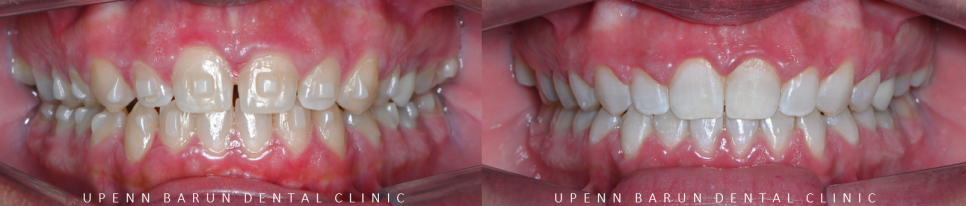

인비절라인 교정을 통해

앞니가 바르게 배열되면서

앞니의 외상을 줄여주고

치아사이의 공간을 닫을 뿐만 아니라

위, 아랫니의 교합관계도 개선이 되었습니다.

그리고 치아가 한층더 밝아진것 보이시나요??

두번째 클린체크를 완료하고 나서는

미백 맛집인 유펜바른치과의

미백치료와 함께 마무리해드렸습니다 ><

환자분께서 웃을때 도드라져 보이던 앞니사이의 틈이

유펜바른치과의 인비절라인으로 해결되면서

웃을때 보다 단정하고 부드러운 이미지로 변화되었습니다~!